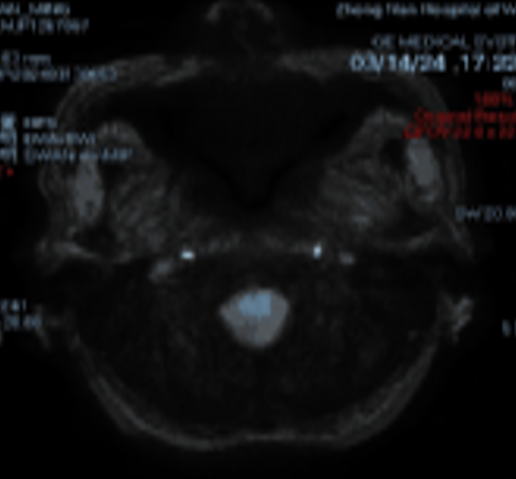

DWI、SWI

动脉长鞘怎么置入桡路大腔,超薄无伤 | EasyMax™ Pro长鞘经桡入路辅助行颈内动脉支架植入术_https://www.jmylbn.com_新闻资讯_第4张

动脉长鞘怎么置入桡路大腔,超薄无伤 | EasyMax™ Pro长鞘经桡入路辅助行颈内动脉支架植入术_https://www.jmylbn.com_新闻资讯_第5张

磁共振:左侧大脑半球低灌注。